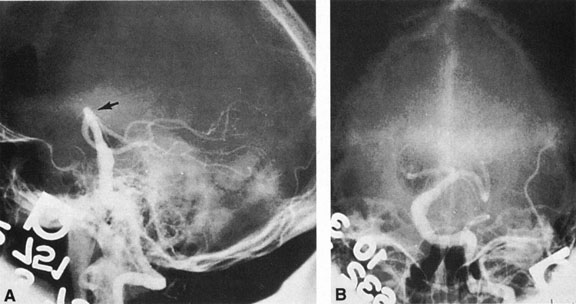

Tortuous or redundant basilar arteries are not uncommon in the older age group. Occasionally, gross dilation or ectasia develops so that the basilar artery acts as a mass in the posterior fossa. This phenomenon produces signs of low-pressure hydrocephalus, cranial nerve palsies, and long tract and sensory signs and may even simulate a cerebellopontine angle tumor or tumor at the foramen magnum.58 It is possible to diagnose such lesions with CT59 or MRI60 but angiography is definitive (Fig. 6). The association of insidious multiple cranial nerve palsies and long tract signs referable to a brainstem level, in an elderly patient with evidence of atherosclerosis, should make fusiform basilar artery dilation a diagnostic consideration.

Fig. 6. Fusiform basilar dilation. A: Lateral projection vertebral arteriogram showing a widened basilar artery (arrow) projecting beyond level of dorsum sellae. B: Anteroposterior projection showing a widened and tortuous basilar artery.